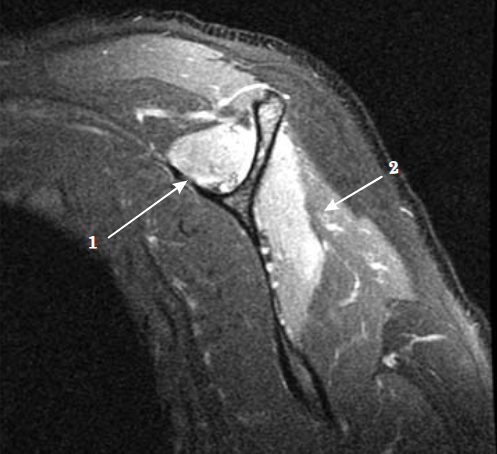

- Resonancia magnética: Cuando se sospeche de otra causa potencial (neoplasia, hernia cervical…) y nos puede mostrar si se realiza el estudio sobre la musculatura afectada. Mostrando patrones de edema difuso en fases iniciales y el aumento de infiltración grasa intramuscular en fase tardía.

Imágenes de este caso clínico